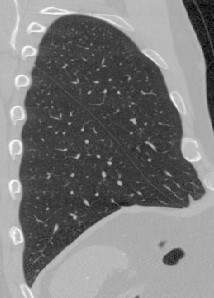

To illustrate the patterns in the radiomic biomarker information obtained across the range of disease, we examine the values from three representative individuals, from healthy, mildly abnormal (Sarc A), and very abnormal (Sarc B) CT scans. As disease becomes more apparent on the CT slices (from healthy to very abnormal) (Figure 1), the values for Moran’s increase. In contrast, the values for fractal dimension and Geary’s C decrease (Tables 3, 4, 5). An increase in Moran’s and a decrease in Geary’s C are indicative of more positive spatial autocorrelation; a decrease in fractal dimension is indicative of smoother structures. The trend in these parameters are clinically important, since we expect to see more positive spatial autocorrelation and smoother structures in CT slices as disease worsens.